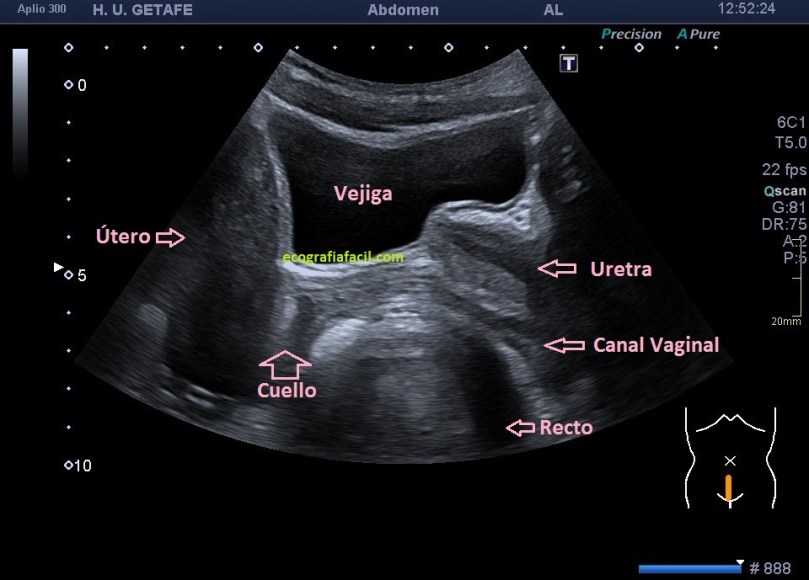

Este protocolo de exploración lo tienes detallado en post anteriores, te dejo el índice del blog para que puedas consultarlo, es el Post 59. Te dejo una imagen de normalidad como base para el caso de hoy:

Corte sagital medio de la pelvis femenina con detalle de la anatomía básica de la ecoarquitectura a este nivel.